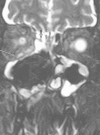

We present a case of rhino-orbitary mucormycosis which progressed despite liposomal amphotericin and early surgical debridement. Combined echinocandin and high dose liposomal amphotericin, repeated debridement, prolonged therapy with hyperbaric oxygen and continued therapy with posaconazole, along with strict diabetic control, allowed cure without disfigurement.